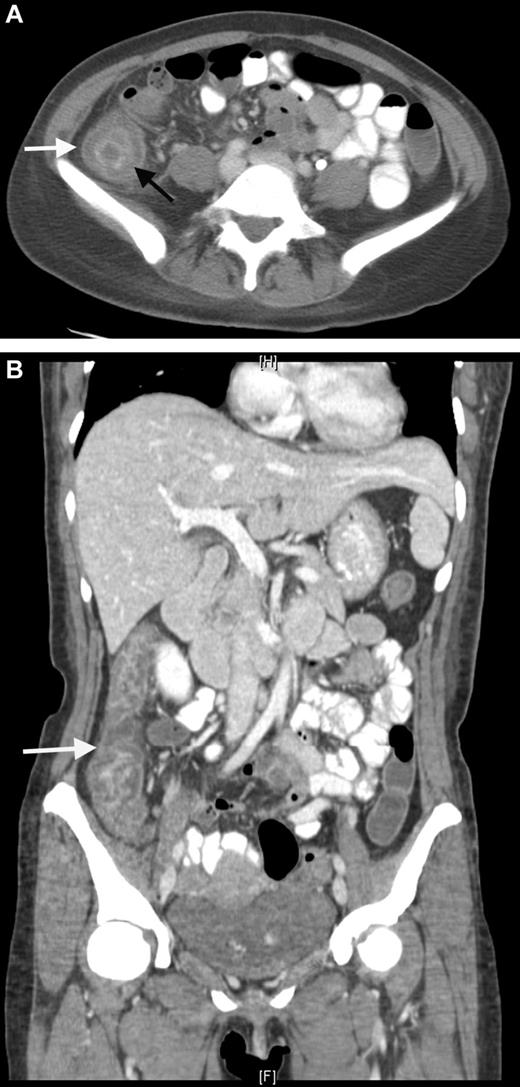

A 35-year-old man with B-lineage ALL is treated with a standard ALL protocol.55 On day 17 of induction, Escherichia coli L-asparaginase (L-ASP) is started at a dose of 10 000 units/day in combination with prophylactic subcutaneous low molecular weight heparin (LMWH). Pretreatment thrombin time, partial thromboplastin time, fibrinogen, and D-dimer levels are normal. On day 9 of L-ASP, he presents with generalized seizure, right-sided limb weakness, and slurred speech. CT scan discloses extensive sagittal sinus thrombosis (Figure 2). L-ASP treatment is discontinued and full dose heparin is initiated. There is no evidence of inherited thrombophilia.

CT scan. Sagittal plane demonstrating sagittal sinus. The arrow indicates the filling defect corresponding to sagittal sinus thrombosis.

We treat CNS thrombosis with full-dose heparin coupled with intensive cryoprecipitate and platelet transfusion support. Sagittal sinus thrombosis is often accompanied by increased intracranial pressure and secondary hemorrhagic infarct. We continue heparin, even in the presence of such hemorrhage with blood product support and frequent CT/MRI monitoring, because the primary event is thrombosis. Importantly, for the same reason, L-ASP may be resumed at lower doses if toxicity was not greater than grade 3 and completely resolved.59,65